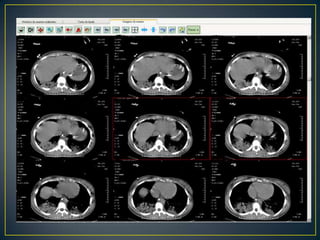

CONDUTASolicitado:Hemograma, bioquímica, PCR, LDLVDRLVHST4 livre, TSHAldolaseCombs direta e indiretaSorologia para dengue e hepatite CFunção HepáticaGasometria com lactatoHIVPunção LombarTCTXPRESCRITO HIDANTALPRESCRITO MACRO CONTINUA

CONDUTASolicitado:Hemograma, bioquímica, PCR,LDLVDRLVHST4 livre, TSHAldolaseCombs direta e indiretaSorologia para dengue e hepatite CFunção HepáticaGasometria com lactatoHIVPunção LombarTCTXPRESCRITO HIDANTALPRESCRITO MACRO CONTINUA